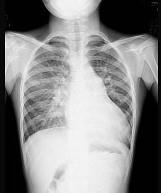

问题 5岁男孩,诊断先心病室间隔缺损,拍胸部正位片如图所示,你认为下列关于肺部正确的结论是 ( )

选项 A、间质性肺水肿 B、肺充血 C、正常肺 D、肺泡性肺水肿 E、肺淤血

答案 B